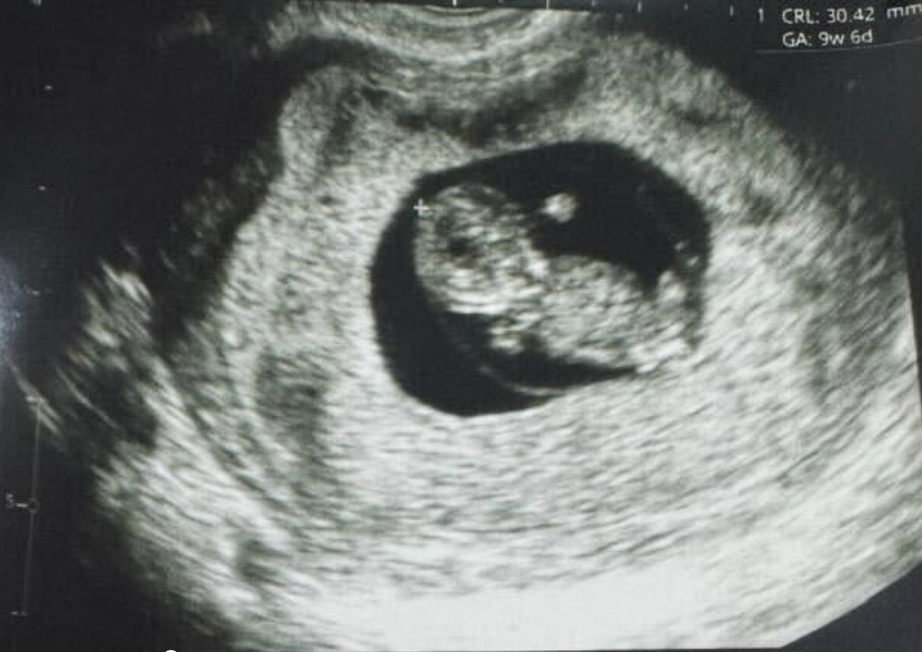

紐約(?BUSINESS WIRE?)致力于推動女性健康治療方案發(fā)展的生物技術(shù)公司Gameto與2024年12月16日宣布,該公司利用 Fertilo 實現(xiàn)了全球首例活產(chǎn)。此次分娩在秘魯利馬的圣伊莎貝爾診所進(jìn)行。

“通過更少的注射和更溫和、侵入性更低的卵子提取過程,它讓我在這段非常私人的旅程中充滿希望和安慰。Fertilo 的創(chuàng)新方法使身體體驗更加輕松,也減輕了許多激素注射帶來的情感負(fù)擔(dān)。我非常感謝 Pranor 診所和 Gameto 團(tuán)隊的關(guān)懷和奉獻(xiàn),讓我擁有一個家庭的夢想成為現(xiàn)實。”通過 Fertilo 出生的第一個孩子的母親說道。